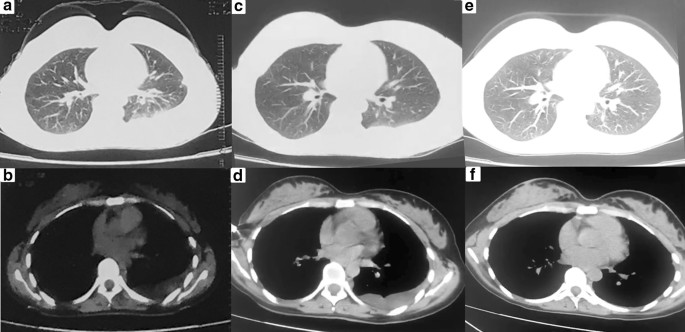

We report the case of a 32-year-old non-smoker female, who presented with mild dyspnea for two weeks. She denied cough, hemoptysis, fever and weight loss. Serologic tumor markers, including carcinoembryonic antigen (CEA) and α-fetoprotein (AFP), did not reveal any abnormalities. Tuberculin purified protein derivative (PPD) test of the patient was negative. A computed tomography scan (CT) of the chest revealed left pleural effusion, and there was no evidence of mediastinal lymphadenopathy and the lung fields were clear (Fig. 1a, b). Although undergoing repeatedly thoracentesis, the hemorrhagic pleural effusion was recurrent refilling. The routine biochemical test of pleural effusion showed that it was exudative, while no malignancy was detected on cytology examination. Thus, single port video-assisted thoracoscopy (VATS) was then performed. Thoracoscope showed a large number of nodules arising from the parietal pleura, with a tenacious texture and a clear margin. Biopsy was performed on multiple nodules, with a little bleeding (Fig. 2). Microscopic examination revealed the nodules comprised a conglomerate of capillary vessels, and some of the vascular spaces lined by proliferating endothelial cells. No significant atypia was found in the lining endothelial cells (Fig. 3a). Immunohistochemical (IHC) analysis showed CD31 and erythroblast transformation specific regulated gene-1(ERG) positive, and Ki-67 proliferation index was 2% (Fig. 3b–d). The biopsy was suggestive of capillary hemangioma. Dexamethasone (10 mg/day)was injected into the thoracic cavity for three consecutive days, and then the patient began to receive prednisone acetate (30 mg/day). Unfortunately, both topical and systemic dexamethasone were failure to control pleural effusion. The chest CT scan showed that medium-volume still exist after 4 weeks of oral corticosteroids (Fig. 1c, d). Hence, the patient stopped corticosteroids and switched to oral azathioprine 100 mg ever day. No side effect associated with azathioprine occurred. The patient was followed up regularly and the pleural effusion was gradually reduced. At the 12 months of follow up, reexamination with CT scan revealed no pleural effusion (Fig. 1e, f).